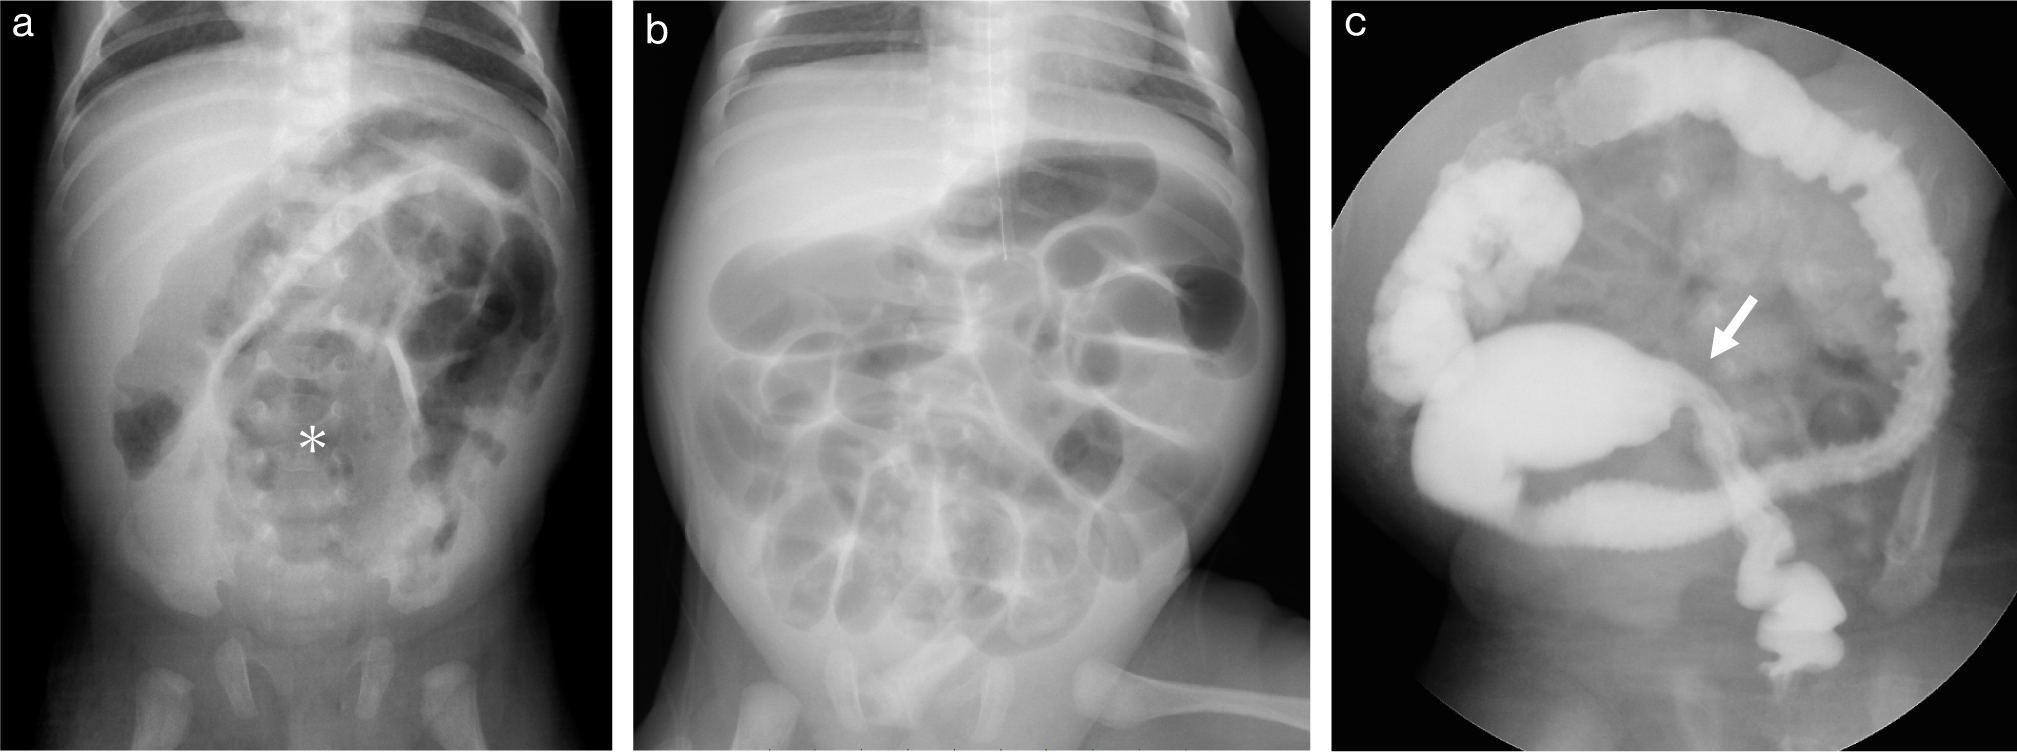

腹部レントゲンでは最も重要な初期検査で,びまん性に拡張した腸管のガス像および,本症に特徴的な腸管壁内ガス(pneumatosis intestinalis),門脈内ガスの有無を確認する(Fig. 11a).また,腹腔内遊離ガス(フリーエア)の存在は消化管穿孔の診断の下,外科手術の適応となるため重要である.

日齢17で壊死性腸炎を発症した男児

a.腹部レントゲン所見.びまん性に腸管の拡張を認め,腸管壁内気腫を認める.門脈本幹から肝内の門脈分枝にかけてair densityを認め,門脈内ガスと考えられる.

b.腹部エコー所見.肝内に無数の高エコースポットを認め,門脈内ガスの所見である.

エコーでは門脈内ガスが肝内で高輝度に描出される(Fig. 11b).腸管壁の血流評価や腹水の検出なども行う.